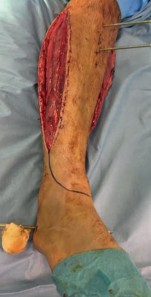

The patho-epidemiology of these injuries is inextricably linked to the incidence of acute compartment syndrome. High-energy axial loads result in rapid swelling, hemorrhage, and edema within the unyielding fascial compartments of the leg. As demonstrated in our reference case, clinical examination often reveals a tense, swollen limb necessitating an immediate four-compartment fasciotomy. The dual-incision technique remains the standard of care to decompress the anterior, lateral, superficial posterior, and deep posterior compartments. The presence of fasciotomy wounds further complicates the surgical approach for definitive internal fixation, requiring strict adherence to the principles of damage control orthopedics (DCO).

Image

In the setting of acute compartment syndrome, the presence of fasciotomy wounds fundamentally alters the surgical timeline. The primary goal is the preservation of limb viability through immediate decompression. Once the external fixator is applied, the fasciotomy wounds are typically managed with negative pressure wound therapy (NPWT) or vessel loops (shoelace technique) to facilitate gradual closure. Definitive internal fixation must be delayed until the soft tissue envelope is deemed capable of withstanding further surgical insult, which often takes 10 to 21 days.

The surgical approach must be carefully orchestrated, particularly in a patient with pre-existing fasciotomy incisions. If an anterolateral approach is selected, the incision is typically centered over the interval between the tibialis anterior and the extensor hallucis longus (EHL), or between the EHL and the extensor digitorum longus (EDL). The superficial peroneal nerve must be meticulously identified and protected, as it often crosses the surgical field in the distal third of the leg. The anterior tibial artery and deep peroneal nerve are retracted laterally with the EDL.

If a medial approach is utilized, the incision is made just medial to the tibial crest, avoiding the saphenous vein and nerve. The full-thickness fasciocutaneous flap is elevated off the periosteum to minimize devascularization. In cases where compartment syndrome fasciotomies have been performed, the surgeon must often incorporate the existing traumatic or surgical incisions into the definitive surgical approach to avoid creating narrow skin bridges that are prone to necrosis.